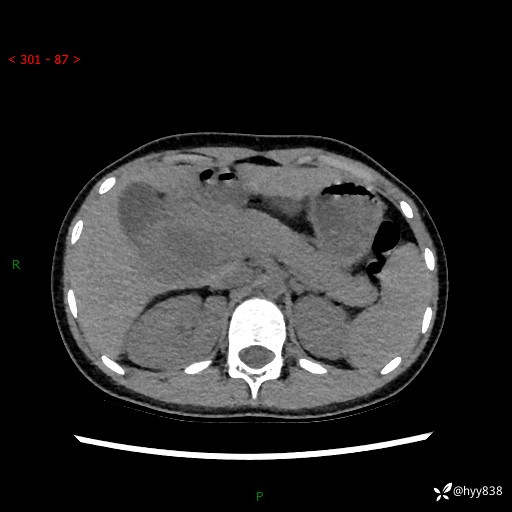

性别:女

年龄:13岁

简要病史:超声提示上腹部巨大包块

上腹部CT平扫